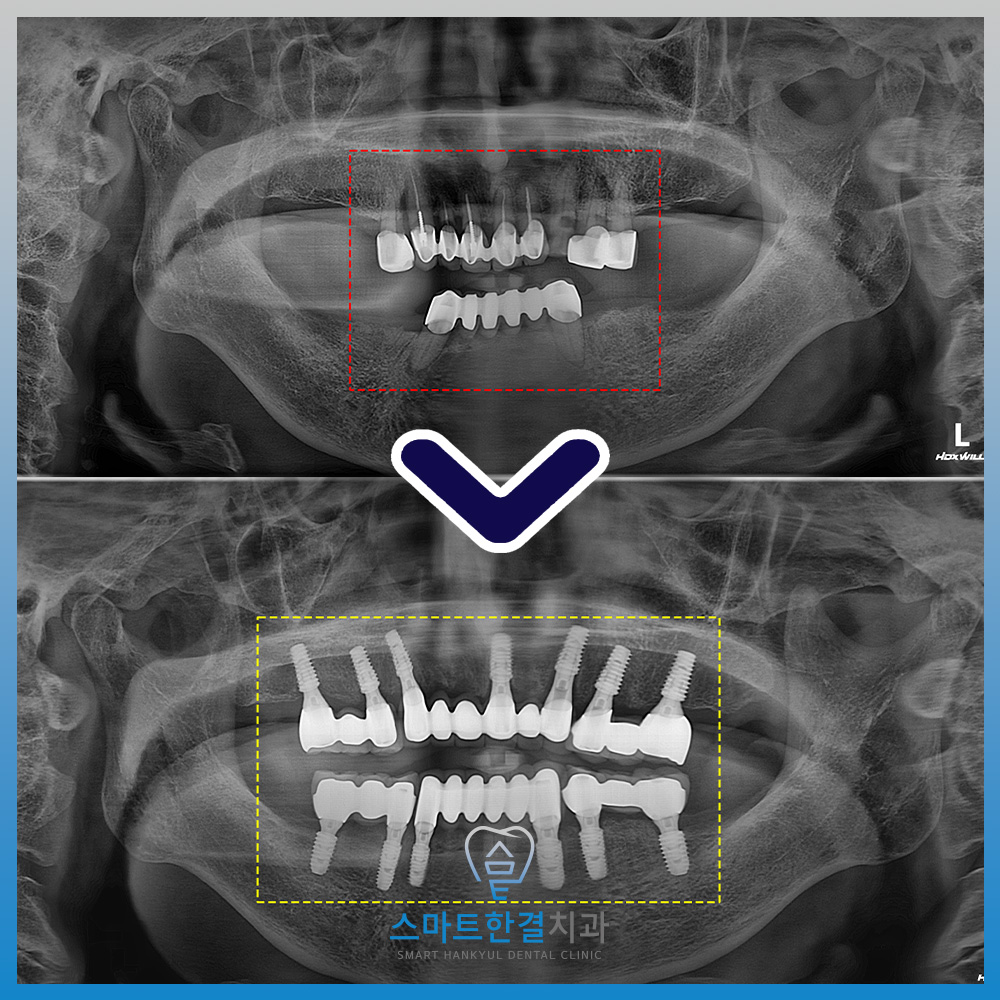

수원치과 스마트한결치과의

전체 임플란트 전후 사진이에요.

환자분께서는 전체 임플란트를 받아보신 후

진작에 치료할걸 그랬다며

이전과 비교해 훨씬 편해졌고

식사할 때도 불편함이 거의 없다고

만족감을 표현해 주셨어요.